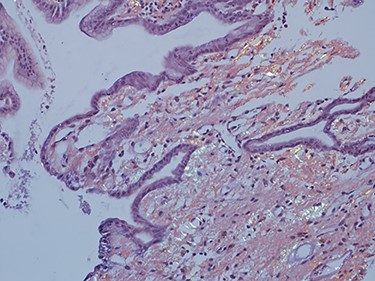

As work up for his abdominal pain and anemia he underwent gastroscopy on 29 October 2020 that revealed congested and nodular gastric mucosa (mass-like) and at lesser extend in the first and second part of duodenum (Figs 1 and 2). Biopsies were taken from the gastric lesion and duodenum. Histopathological findings from gastric mass and duodenum showed marked stromal hyalinosis, which appeared as a cellular pink material on H&E stain (Figs 3 and 5). Congo red stain (amyloid stain) showed apple green birefringence under polarized light on both gastric and duodenal biopsies (Figs 4 and 6).

High power of duodenal biopsy showing stromal hyalinosis (H&E x 20).